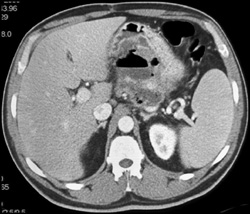

Acute Pancreatitis